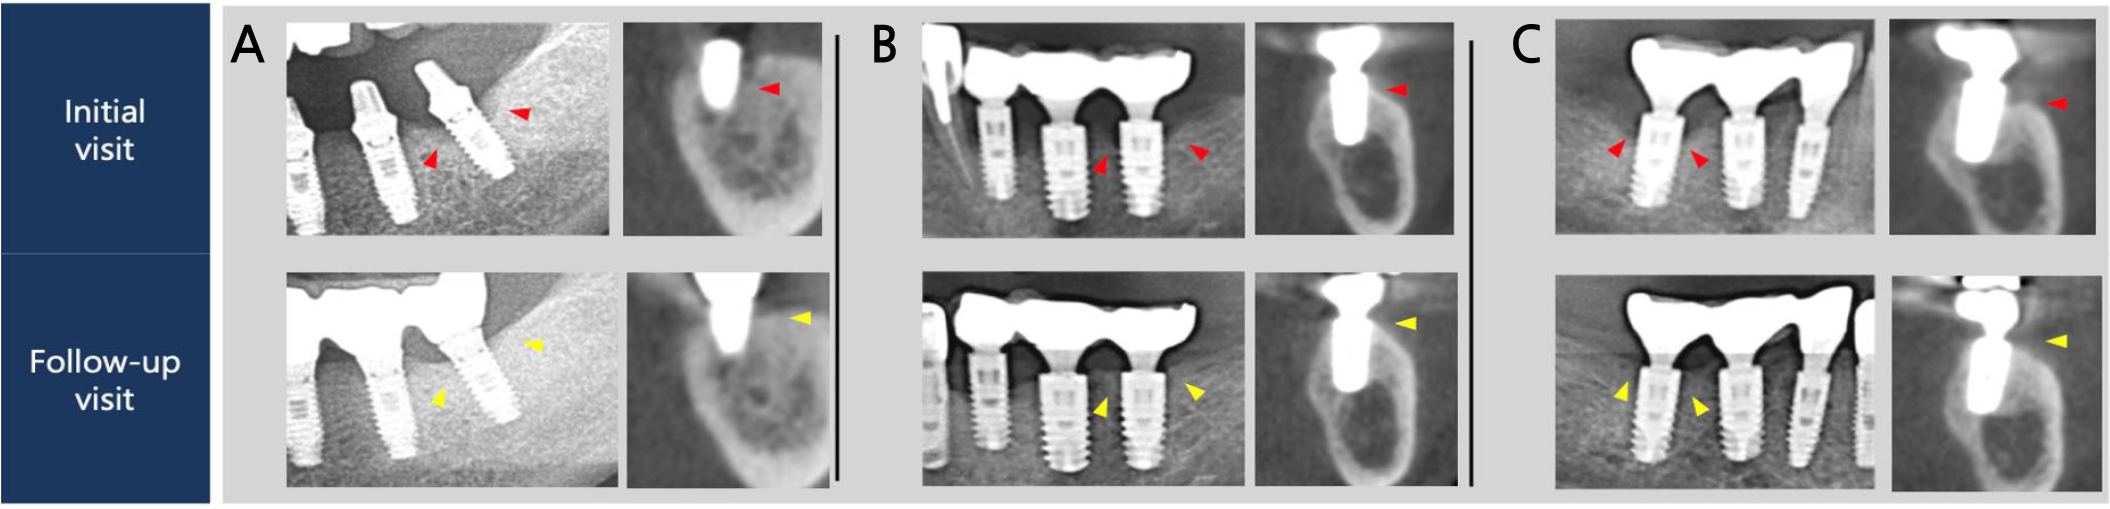

Fig. 5.

Regions of interest of panoramic graphs and cross sectional views obtained from cone-beam computed tomography. (A) Mandibular left first molar of Case 1. (B) Mandibular left second molar of Case 2. (C) Mandibular right first molar of Case 2. Red and yellow arrows show marginal bone levels at the intital and follow-up visits, respectively.